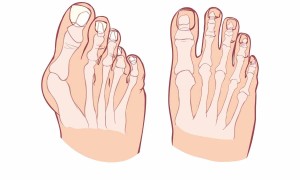

Bu kategoride, kasların çalışma prensipleri, kas geliştirme yöntemleri, kas yaralanmaları ve rehabilitasyonu gibi konulara odaklanan içerikler bulunmaktadır. Kemik sistemi ile ilgili makalelerde, kemiklerin yapıları, büyüme süreçleri, kemik sağlığını etkileyen faktörler ve kemik hastalıkları gibi konular ele alınır. Aynı zamanda, eklemlerin anatomisi, eklemlerle ilgili yaygın sorunlar ve eklem sağlığını koruma stratejileri gibi içeriklere de yer verilir.

Bu kategori, sporcular için kas gelişimi ve performans artışı, yaşlanma sürecinde kemik sağlığının korunması, ortak eklem rahatsızlıkları ve rehabilitasyonu gibi konularda geniş bir bilgi kaynağı sunar. Ayrıca, ergonomi, düzgün beslenme ve egzersiz gibi faktörlerin kas, kemik ve eklem sağlığı üzerindeki etkilerini anlatan içeriklere de yer verilir.